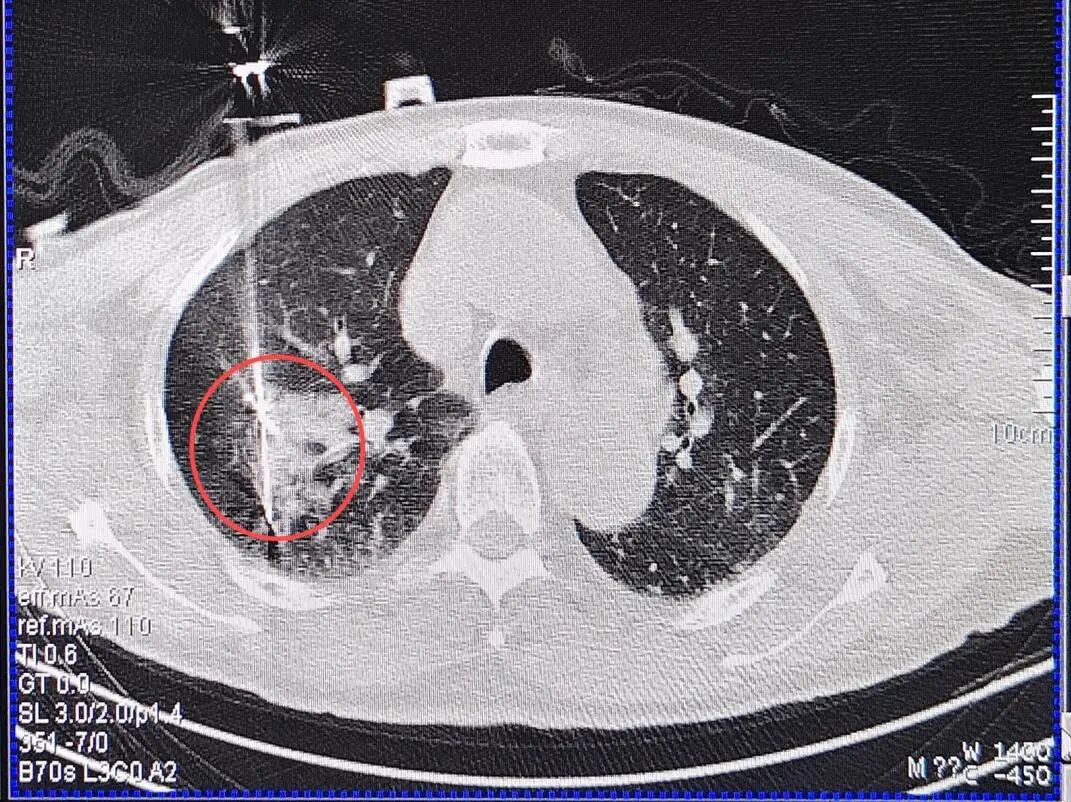

2月21日,贵州航天医院国务院政府特殊津贴专家、二级教授、学科带头人廖江荣教授呼吸团队再次为一名81岁的患者成功实施AI机器人辅助经皮穿刺氩氦刀冷冻消融术,仅用40分钟就完成对肺结节的“精准狙击”。 “AI机器人不仅提供高精度的穿刺方案,还能通过机械臂稳定执行,避免人工操作的手部震颤误差。”廖江荣教授介绍。 传统经皮穿刺氩氦刀冷冻消融术高度依赖医生经验,面对复杂病灶时,常面临“定位难、穿刺深、耗时长”的挑战。在此次手术中,呼吸团队借助AI机器人智能影像分析、穿刺计划系统,对患者肺结节进行了多视角的立体三维重建,精确定位了病灶,并规划出最佳进针位置、角度和轨迹,通过AI机器人可视影像系统和机械臂穿刺系统的引导,“一针”就穿刺进入病灶预定位置进行冷冻消融,手术过程仅40分钟。 术 前 机器人机械臂定位中 完成定位 消融针通过机械臂导引孔精准到达病灶位置 冷冻消融中 消融后,晕征范围完全覆盖结节位置 此次接受手术的是一位81岁的高龄患者,肺结节最大径达2.3cm,由于身体条件限制,传统手术风险较高,在AI机器人辅助下的氩氦刀冷冻消融术完成了病灶的精准消融。 什么是AI机器人辅助消融治疗? AI机器人辅助消融治疗术是一种较为先进精准、微创的技术,医生通过AI机器人精密的操作系统,以毫米级的精确度操控冷冻或微波探针,直达靶点,释放低温或高温摧毁病变组织,同时明显提升了手术的安全性和效率。 与外科手术相比,消融治疗的创伤程度要轻许多,极大地减轻了患者的手术痛苦,缩短了康复周期。 与徒手穿刺相比,AI机器人规划和辅助引导定位具有更稳定、更精准、更安全的优势,避免反复调整穿刺方向与深度,造成更多的伤害。 如果病灶靠近肺内大的血管、气管或肺外的重要脏器,AI机器人辅助消融能最大限度避开高危部位,保护周围健康肺组织不受损伤。 什么是氩氦刀冷冻消融? 氩氦刀冷冻消融是通过将一根1.7-3毫米的中空钢针,穿刺进入病灶,先注入氩气,迅速降温至-160摄氏度,冰冻肿瘤数分钟,再注入氦气,快速升温至20-30摄氏度,共历经3个冷冻、复温循环过程,对病灶组织进行物理性杀灭。 主要适用于 2.重要脏器功能不全,体质过弱,不宜手术的患者。 3.术后复发、转移性癌灶、多发癌灶的患者。 4.晚期患者延长生命提高生存质量的姑息性治疗。 5.因各种原因拒绝手术的患者。 贵州航天医院呼吸与危重症医学科微创介入诊疗技术已达到国内前列,省内领先水平,是亚洲冷冻治疗学会常务理事单位,并获批成立遵义市肺结节多学科(MDT)微创诊疗中心。 肺结节MDT门诊出诊信息 出诊时间: 周一至周五 8:00--12:00;14:00--17:00 出诊地点: 遵义市肺结节多学科微创诊疗中心(MDT)门诊(贵州航天医院呼吸综合楼1楼) 呼吸与危重症医学科与心胸外科、医学影像科、麻醉科等科室建立了多学科(MDT)会诊机制,结合患者情况,通过采取外科手术、冷、热消融等多种治疗手段,帮助患者安全、有效、精准、科学、快速治疗肺结节,单次消融手术时间约半小时左右,几乎没有疼痛,且并发症少,3-5天即可出院,有效减少了患者因开刀手术需长时间恢复的痛苦。 注:图片来源于网络,如有侵权,请联系删除。 贵州航天医院 呼吸与危重症医学科专家团队 廖江荣 国务院政府特殊津贴专家 二级教授 主任医师 呼吸与危重症医学科 学科带头人 国家级学术任职: 第二届中国医药教育协会介入微创专业委员会呼吸分会副主任委员 中国抗癌协会肿瘤微创治疗专业委员会常务委员 中国防痨协会结核病转化医学专业分会常务委员 第一届中国人体健康科技促进会呼吸介入专委会常务委员 中国医疗保健国际交流促进会结核病学分会第三届委员会常务委员 中国抗癌协会肿瘤微创治疗专业委员会粒子治疗学组第四届委员会委员 中华医学会结核临床专业委员会内镜介入委员 中华医学会放射学分会第十五届委员会介入学组呼吸系统介入专业委员会委员 北京健康促进会中青年专家委员会胸部疾病精准活检分委会副主任委员 中国医师协会介入医师分会第二届委员会肿瘤消融专业委员会委员 中国结核病防治综合质量控制专家指导委员会委员 亚洲冷冻治疗学会常务委员 世界内镜医师协会呼吸内镜协会常务理事 内镜临床诊疗质量评价专家委员会委员 “西部呼吸介入联盟”副理事长 专业擅长: 呼吸系统(肺)疑难病的诊断及危重病的抢救,呼吸系统(肺)感染性、疑难性疾病介入快速诊断(ROSE),尤其在肺癌、肺小结节早期诊断,肺癌微创综合靶向治疗,难治性、复治性、重症肺结核诊疗,硬质支气管下复杂性气道狭窄诊治,纤支镜介入治疗气道肿瘤、结核、气道狭窄(球囊扩张、支架植入、高频电刀、氩气刀、冷冻、灌洗、注药、微波消融),间质性肺疾病的诊疗上具有极高水平;带领团队勇于创新,在贵州省率先开展多项新技术、新疗法,如CT引导下及纤支镜下I125粒子植入及CT引导下微波、射频消融介入治疗肺癌等多项新技术,带动了贵州省肺部疾病的介入治疗水平提高。 蒋 婷 呼吸与危重症医学科 总负责人 副主任医师 专业擅长:从医20余年,在呼吸系统疾病、介入呼吸病学、肺部结核、肺部肿瘤等方面具有丰富的临床经验和专业技能,尤其是慢性阻塞性肺疾病、支气管扩张、肺结核、耐药肺结核、肺癌、胸腔积液等肺部疾病的诊治、微创介入、危重病患者抢救。 现任中国防痨协会人兽共患结核病专业分会委员,中国女医师协会第一届介入专业委员会委员,贵州省基层呼吸疾病防治联盟-间质性肺疾病联盟委员,贵州省防痨协会第七届理事会理事,贵州省中西医结合学会呼吸专业委员介入呼吸病学组委员,贵州省遵义市中医药学会中西医结合肺病(呼吸)分会副主任委员,贵州省遵义市中医药学会中医肿瘤专业委员会常委;发表论文数篇,参与并主持多项科研项目。 李桂凤 呼吸与危重症医学科 三病区 主任 副主任医师 专业擅长:从事呼吸系统疾病、结核病学、介入呼吸病学、肿瘤综合治疗、呼吸康复等临床工作20余年,擅长呼吸内科常见病、多发病及疑难重症危重病症的诊治,尤其对重症疑难结核及耐药结核病、介入治疗(肺)呼吸系统疾病、呼吸危重病抢救等方面具有较高诊疗水平。 中国防痨协会非结核病专业委员会委员,贵州省中西医结合学会第六届呼吸专业委员会委员,贵州省康复学会睡眠障碍康复专业委员会委员,遵义市呼吸内科医疗质量控制中心委员,遵义市落实民生实事结核病筛查阅片专家组成员;主持及参与实用新型专利3项。 周裕祥 呼吸与危重症医学科 四病区 主任 副主任医师 专业擅长:经皮肺介入、经血管介入诊疗技术。 贵州省中西医结合学会呼吸专业委员会介入呼吸病学组常务委员,中国医师协会呼吸医师分会介入呼吸病学工作委员会呼吸病血管介入学组委员,贵州省中西医结合学会呼吸学分会委员,遵义市医学会放射肿瘤治疗学分会委员,中国医药教育协会介入微创呼吸分会委员,北京健康促进会中青年专家委员会胸部疾病精准活检分委会委员;曾赴重庆医科大学RICU、珠海市人民医院介入科进修学习。 杨 芳 呼吸与危重症医学科 内镜中心 主任 副主任医师 专业擅长:从事临床工作约16年,对呼吸危重病的救治有独到的见解,尤其擅长呼吸系统疾病的介入诊疗,对呼吸内镜下的诊治及经皮肺穿刺诊疗技术具有丰富的临床经验。 亚洲冷冻治疗学会委员,中国医药教育协会介入微创呼吸分会委员,西南结核病医院联盟第二届委员会秘书/委员,贵州省中西医结合学会第六届呼吸科专业委员会委员,贵州省中西医结合学会呼吸专业委员会介入呼吸病学组秘书,贵州省中西医结合学会呼吸专业委员会基层康复学组副组长,贵州水利电力医学科学技术会高原医学分会委员,遵义市中医院学会中西医结合肺病(呼吸)分会秘书/常务委员,遵义市医学会肿瘤学分会(第二届)委员,遵义市医学会放射肿瘤治疗学分会第二届委员;主持及参与科研课题多项,参编著作《呼吸内镜操作技术规范》、《介入结核病学》,发表论文数篇。 贵州航天医院 呼吸与危重症医学科简介 贵州航天医院呼吸与危重症医学科以呼吸危重症和介入呼吸病学为强力推手,以肺部感染性疾病及肺癌、肺小结节的早期精准诊疗、慢性呼吸疾病康复治疗为特色,以人才团队建设为核心的科室发展模式,现已成为省内呼吸疾病治疗规模最大,诊疗项目最全的呼吸疾病品牌科室。是贵州省医学重点学科、临床医学重点专科建设单位,遵义市首批呼吸重点学科、重点专科建设单位。是国家卫健委能力建设和继续教育肿瘤微创介入建设中心、贵州省县级医院微创介入培训中心、遵义市呼吸疾病临床医学中心。是国家呼吸医疗质量控制与管理哨点医院、遵义市呼吸内科专业医疗质量控制中心。是中国医药教育协会介入微创呼吸分会呼吸介入技术培训中心单位;国家卫健委海医会呼吸分会ROSE专委会“诊断性介入肺脏病学快速现场评价”培训基地;中国肺癌防治联盟“贵州航天医院肺结节诊治”分中心,中国人体健康科技促进会呼吸介入技术培训基地,贵州省中西医结合会呼吸学分会呼吸介入专委会主委单位。 基本情况 平均每年开展气管镜诊疗约4000例,经皮肺穿刺介入诊疗近千例,开展的项目包括经支气管镜(软、硬)下冷冻、氩气刀、高频电刀、球囊扩张、支架置入、超声内镜诊疗等气道介入诊疗技术,经皮肺穿刺活检及肿瘤消融术(微波、冷冻)、ROSE技术、内科胸腔镜诊疗及经血管介入诊疗技术,且多项呼吸介入诊疗技术在省内处于领先水平。 诊疗范围 致力于呼吸系统感染性、疑难性疾病的介入快速精准诊疗,肺癌与肺小结节早期精准诊疗水平项目提升。 擅长呼吸系统(肺)疑难病的诊断及危重病的救治,尤其在肺癌、肺小结节的早期诊断,肺癌综合靶向治疗,肺结核综合诊疗,肺部疾病的介入诊疗在省内处于前沿水平。 END